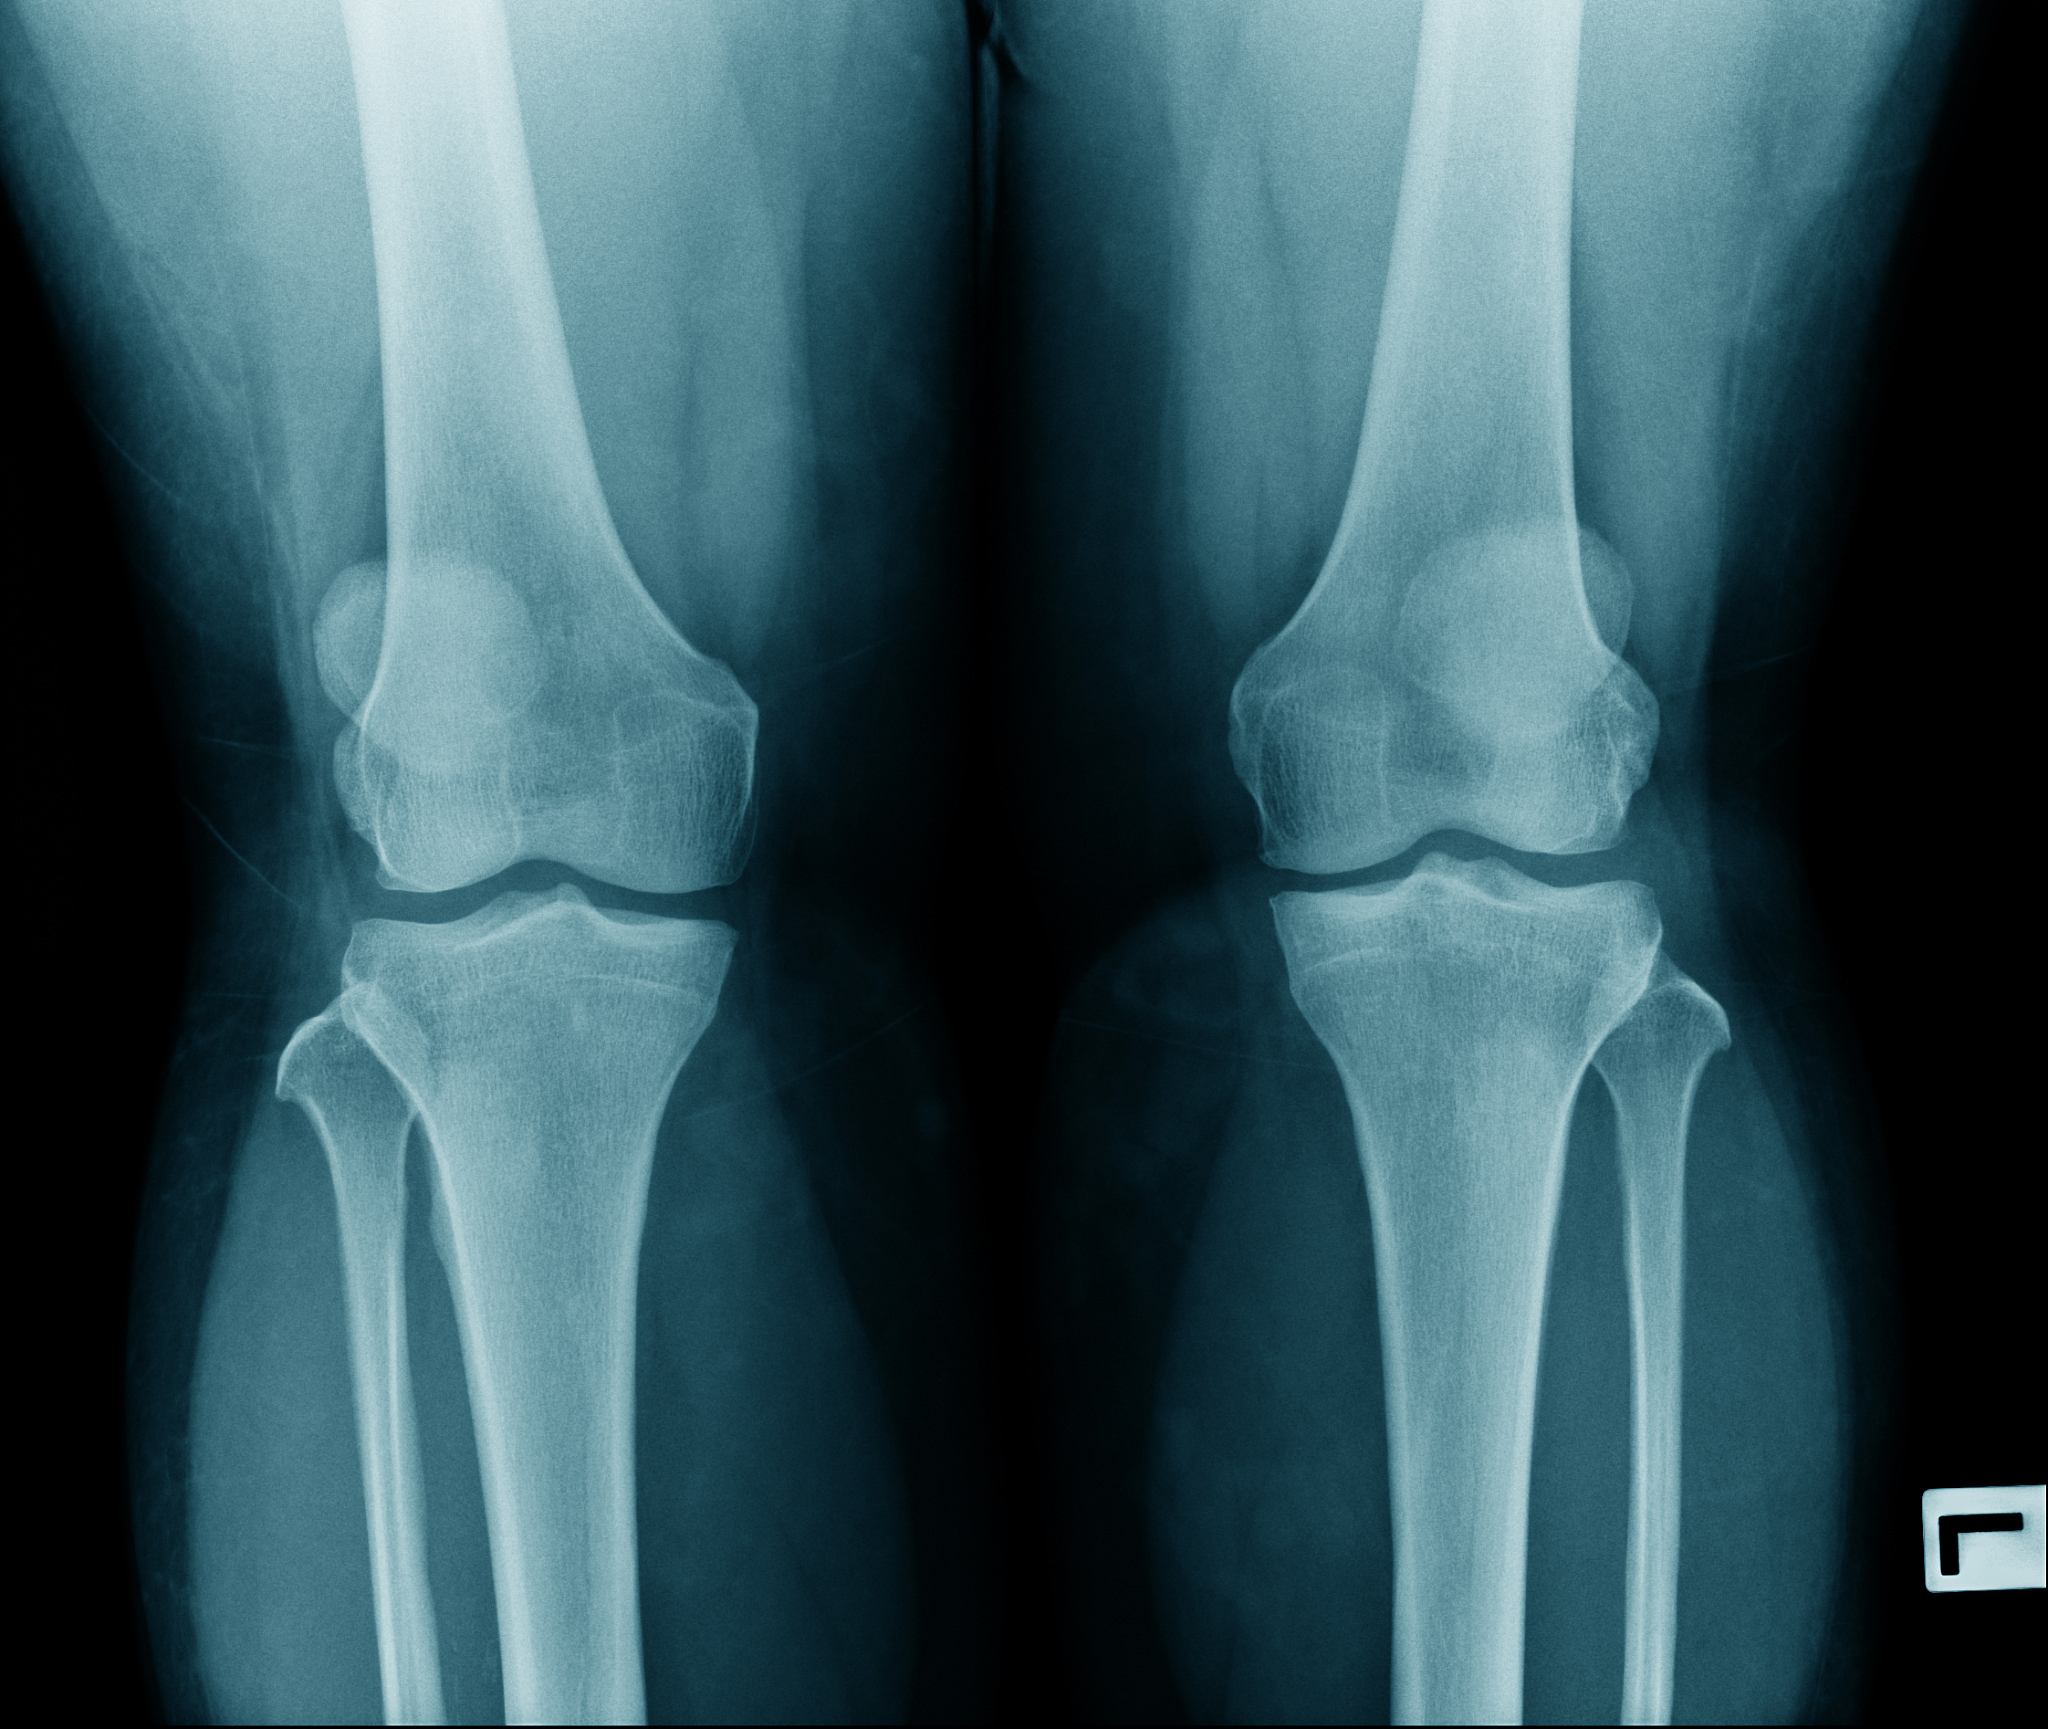

股骨粗隆间骨折是一种常见的骨折类型,尤其在老年人中较为常见。这种骨折是指股骨近端、髋关节下方的骨折,它可能由跌倒或直接撞击引起,对于本身骨质密度较低的老人来说更容易发生。股骨粗隆间骨折对老年人的影响是多方面的,并且十分严重,可能会造成行动不便、引发各种并发症,甚至危及生命。

3. 骨质疏松风险增加: 老年人骨质密度普遍较低,因此骨折的风险也相应增加。股骨粗隆间骨折可能是骨质疏松的一个指标,同时也可能导致进一步的骨质疏松,增加未来再次骨折的风险。

股骨粗隆间骨折的治疗方法取决于骨折的严重程度和患者的整体健康状况。治疗方法包括手术和保守治疗,但手术治疗是大多数股骨粗隆间骨折的主要治疗方法。